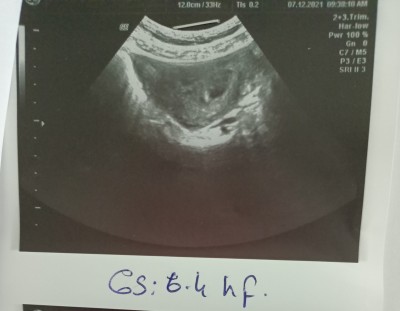

Kızlar merhaba içimi kurcalayan sıkıntı var şimdi 7aralikta keseyi görmek için gittik  5+2 sat a göre ultrason da 6+4 çıktı çok şükür keseyide gördük kalp atışı için 20aralik ta gidicem şimdi Dr hamileliğimi öğrenir öğrenmez coraspirin ve progestan vermişti onlarida içiyorum çok şükür kalp atışı duyuldktan sonra  iğneye baslaticakmis erkenden baslatanlarida duydum oradan biraz kafama takılmıştı hani geç olmasından korkuyorum birazda tedirginim ve ayın 20sinde gittiğimde 8+3 olur inşallah duyarım da oyuzden benim gibi olupta duyan varmı hakkınızı helal edin:'(

Gebelik haftası 6+6